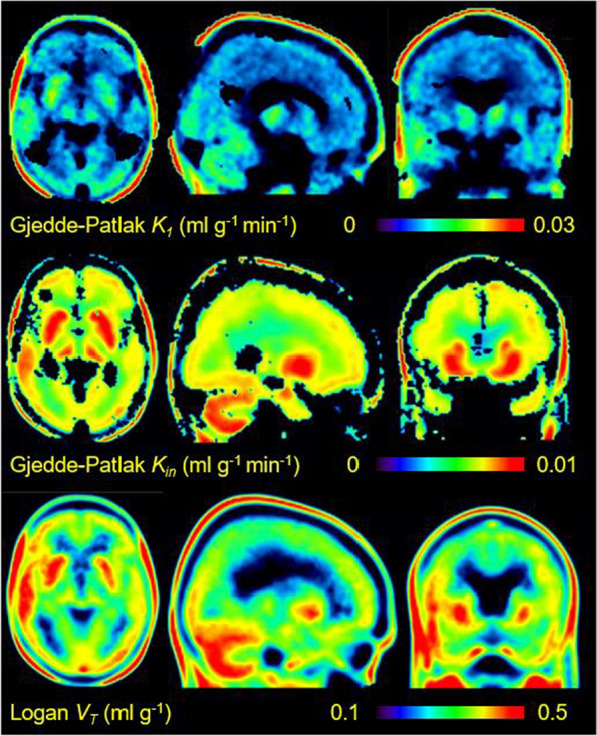

Results: The analyses yielded estimates of regional unidirectional blood-brain clearance K1 (0.00825-0.0244 ml g-1 min-1), net blood-brain clearance Kin (0.00448-0.00913 ml g-1 min-1), and equilibrium distribution volume VT (0.126-0.495 ml g-1), where the lowest values depict white matter, and the highest values cerebellum. In our test of a simplified quantitation of [18F]FET uptake from single frame recordings, i.e., Gjedde-Patlak multilinear graphic analyses of K1 at five min post-injection and Kin at 40 min post injection, results were in good agreement with the analyses from the dynamic recordings (< 10% error).